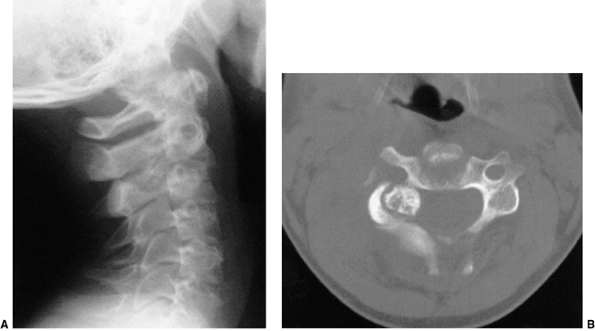

Figure 22.8

This girl, 3 years and 9 months of age, had a history of vertex headaches for 1 year. One month prior to presentation, she developed a painful, left-sided torticollis. A: Plain lateral radiograph shows fusion of C2 and C3 and absence of the ring of C1 with occipitalization. B: Magnetic resonance image (MRI) shows an Arnold-Chiari malformation, with herniation of the cerebellar tonsils into the foramen magnum (arrow). Also note the cordal edema (arrowhead). C: The child underwent an occipital decompression and laminectomy to C3, posterior cervical fusion from the occiput to C4, and halo cast immobilization for 4 months. Flexion and extension lateral radiographs 1 year after treatment show solid incorporation of the fusion from C2 to C4, with dissolution of the graft from the occiput to C2. However, there is no atlantooccipital instability. The child’s symptoms resolved. |